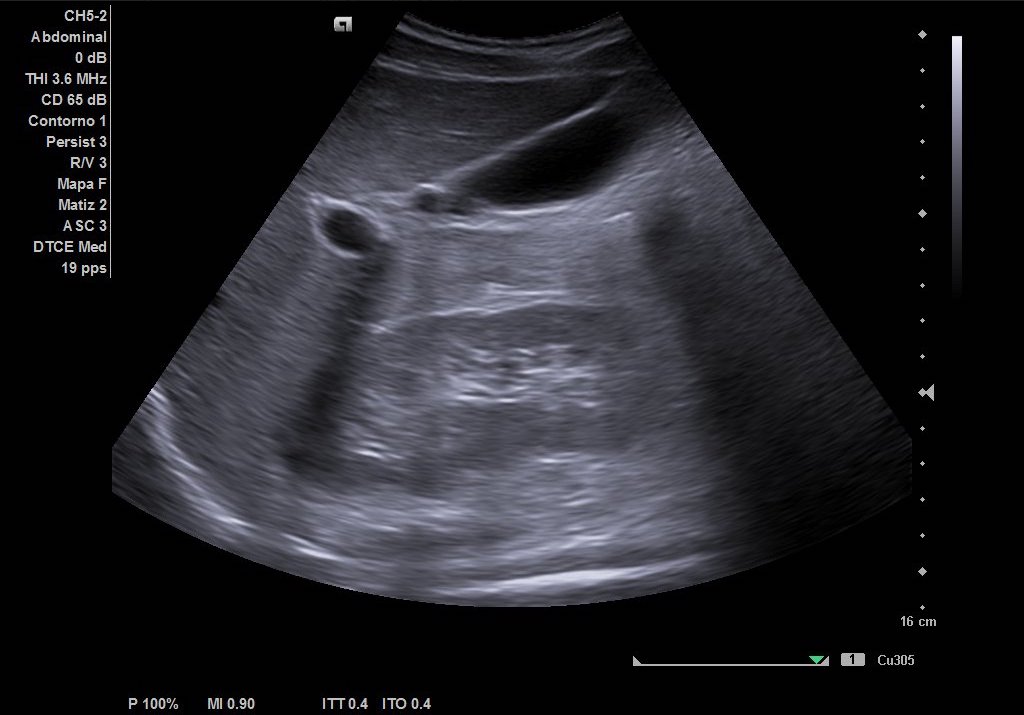

Hallazgos ecográficos

Como hallazgos, observamos dilatación del uréter proximal con hidronefrosis grado II-III. Sin visualización de imágenes compatible con litiasis. Riñón derecho de tamaño y ecoestructura normal sin dilatación de vía excretora. Vejiga vacía y ausencia de liquido libre.

Juicio clínico: Cólico renoutreteral izquierdo con hidronefrosis grado III.